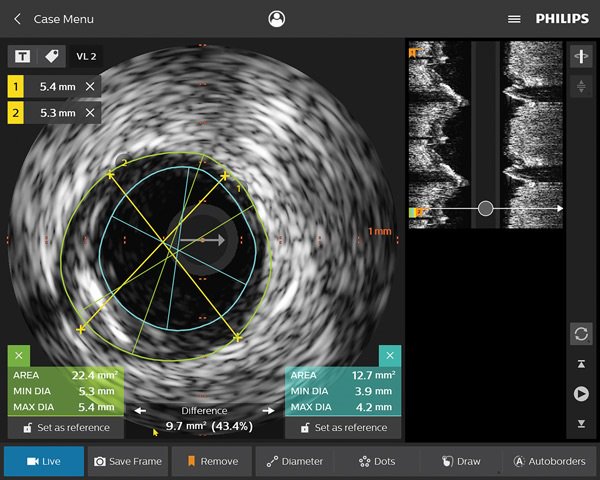

I nostri cateteri per imaging coronarico aiutano a identificare la posizione e valutare la morfologia della placca, incluse le lesioni calcifiche e la presenza di trombi. L'IVUS può essere utilizzato anche per determinare adeguatamente le dimensioni degli stent e confermare l'accuratezza del trattamento.